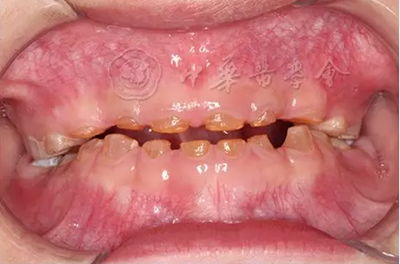

(1)疾病定義及口腔表現(xiàn):是一種罕見的以顱骨和鎖骨發(fā)育不良為主要特征的先天性骨骼系統(tǒng)發(fā)育異常綜合征,又稱Marie-Sainton綜合征,多為常染色體顯性遺傳?;颊呖杀憩F(xiàn)鎖骨單側(cè)或雙側(cè)缺如,顱骨短大,囟門和顱縫寬、延遲閉合或不閉合,面骨較小,眼距寬,鼻梁塌陷??谇槐憩F(xiàn)為腭蓋高拱,部分患者表現(xiàn)為腭裂或腭黏膜下裂。乳牙萌出正常,除第一恒磨牙和其他個(gè)別牙外,多數(shù)恒牙不能正常萌出,影像學(xué)檢查可見牙胚發(fā)育遲緩,乳牙根吸收遲緩,頜骨內(nèi)埋伏多顆額外牙(圖3)。有些癥狀較輕的患者可只表現(xiàn)為牙齒發(fā)育異常。

圖3 10歲顱骨鎖骨發(fā)育不全患兒曲面體層X線片,可見頜骨內(nèi)多顆埋伏額外牙,恒牙胚發(fā)育遲緩,恒牙萌出障礙

(2)治療原則:治療主要是修復(fù)患者的美觀和功能,常需要多學(xué)科綜合治療。替牙期患兒應(yīng)及時(shí)拔除滯留乳牙和額外牙,以促進(jìn)恒牙的正常萌出;對萌出困難的恒牙,可以采用手術(shù)開窗暴露并結(jié)合正畸牽引的方式進(jìn)行治療;無法牽引到位的恒牙可手術(shù)拔除后進(jìn)行義齒修復(fù)。對上頜骨發(fā)育不良的患者,可通過正畸擴(kuò)弓緩解牙列擁擠。